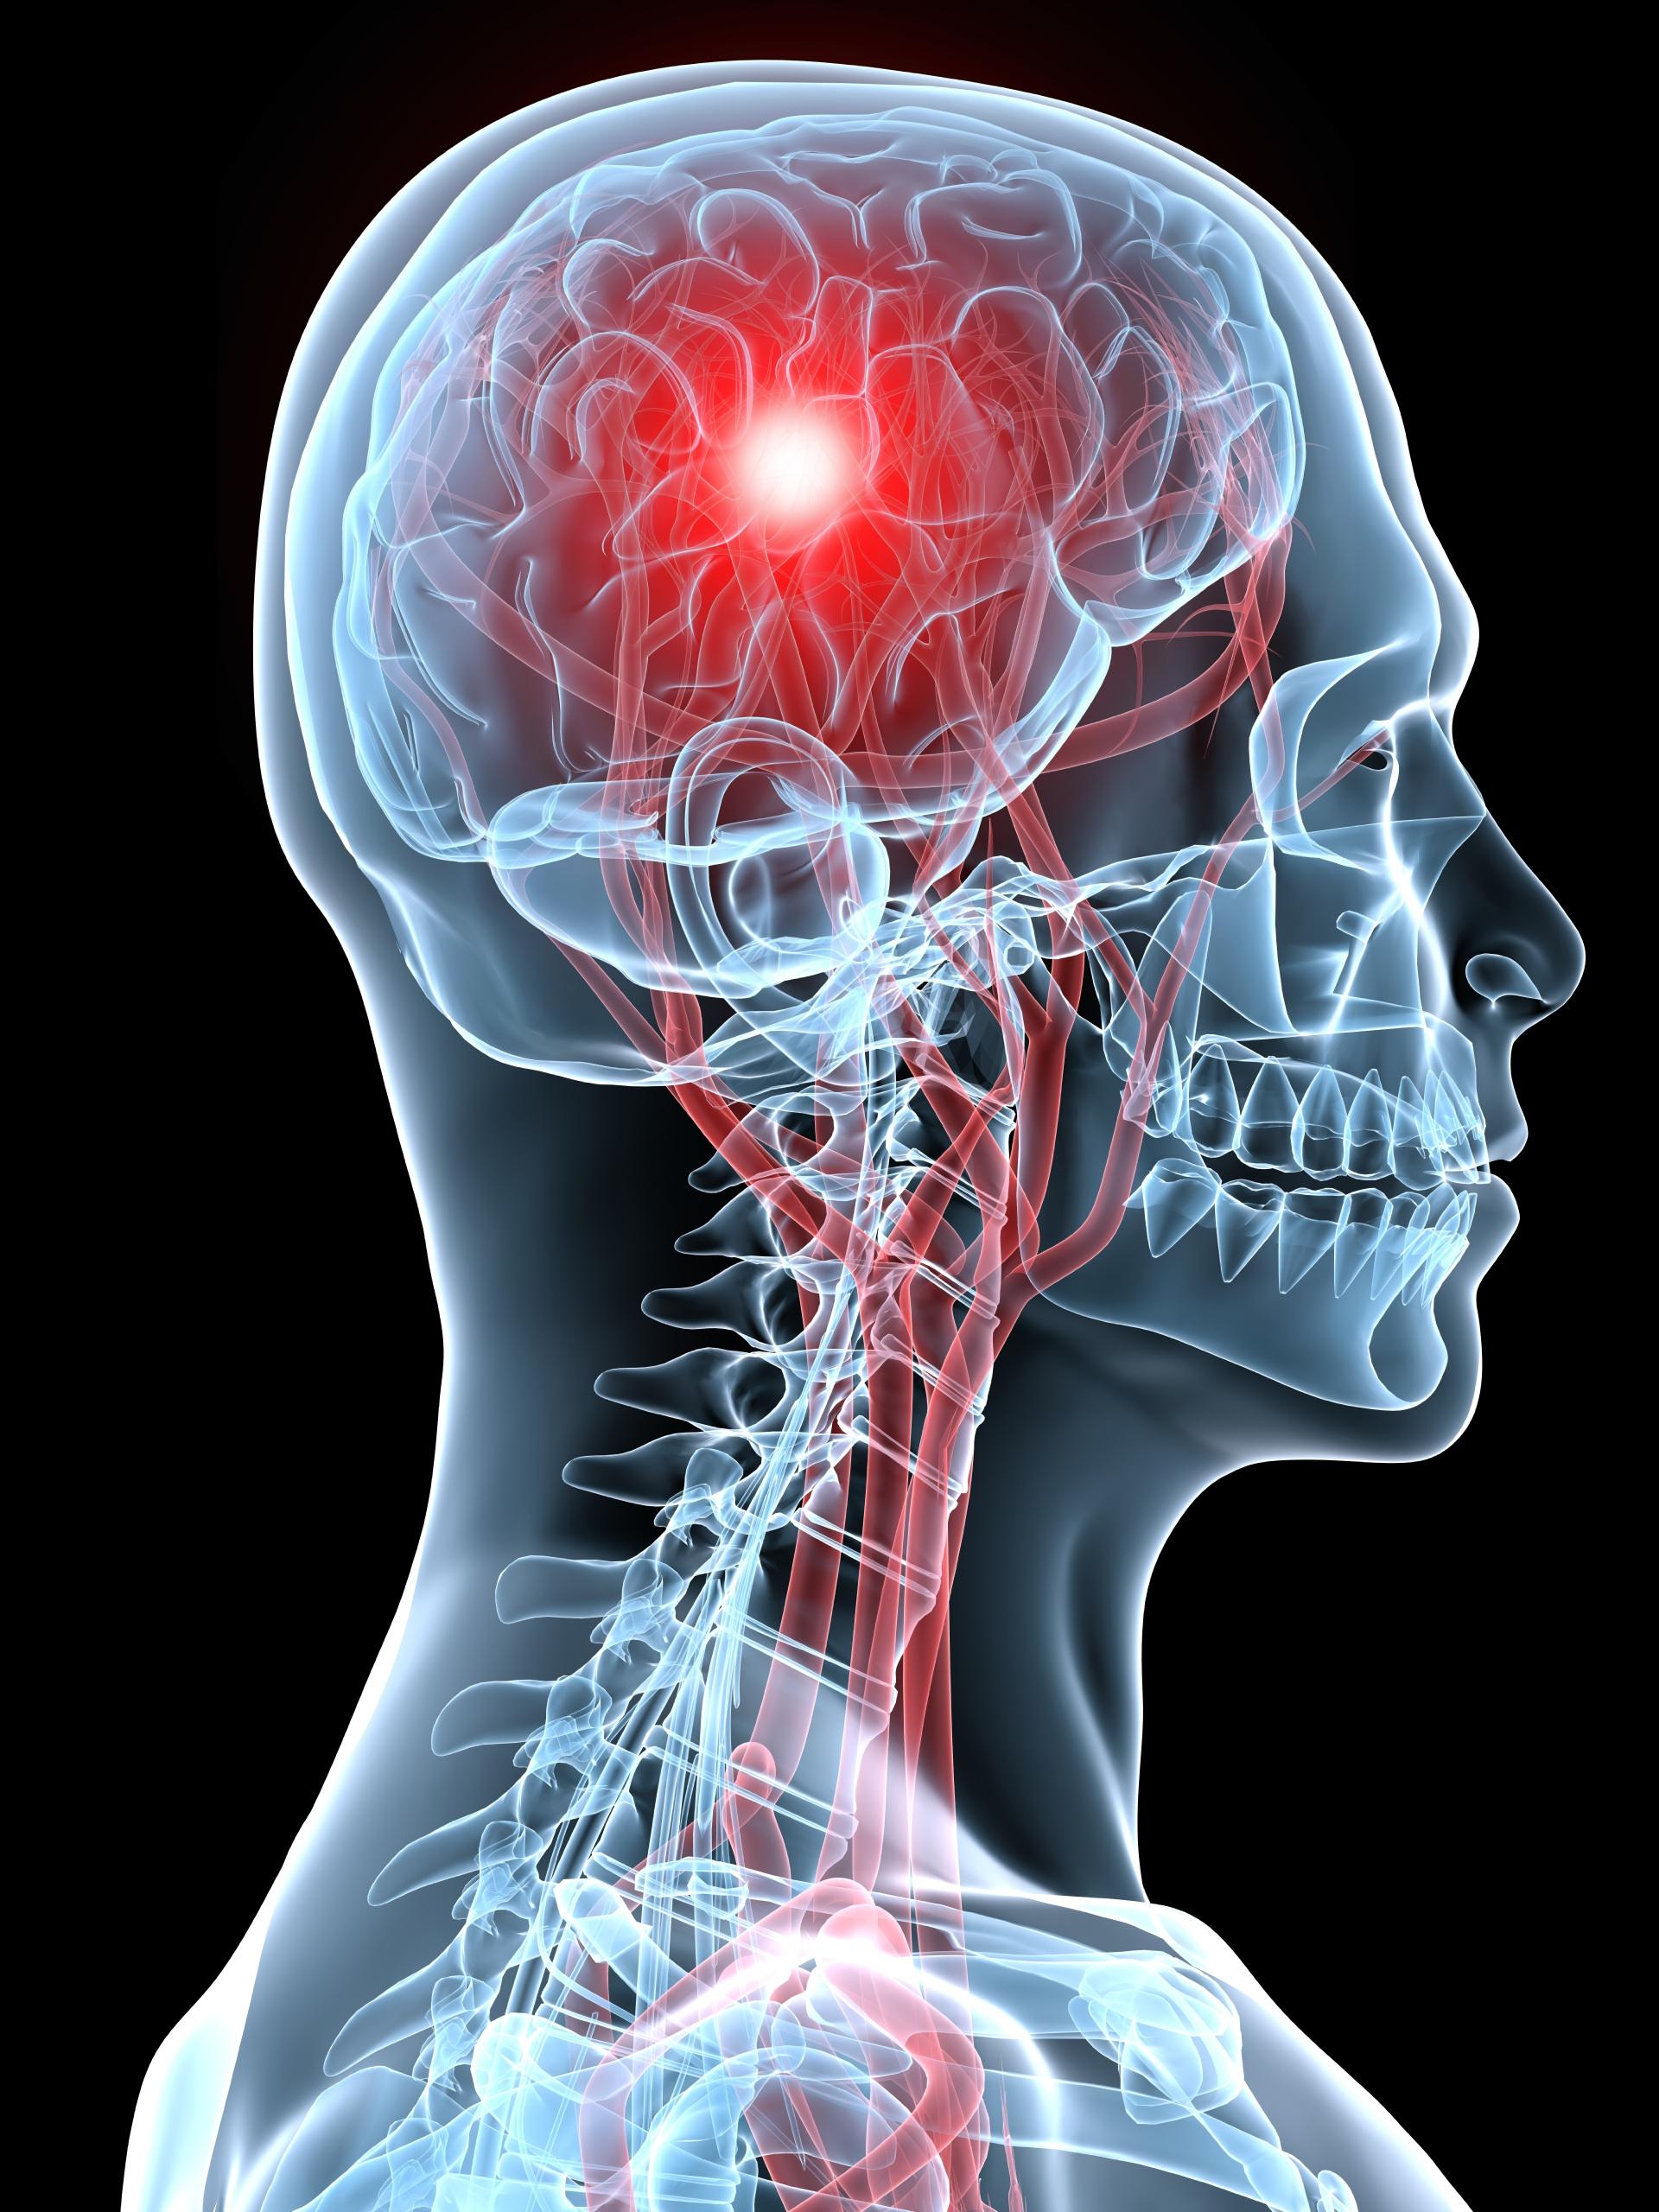

Doctors initially thought she had suffered a seizure. They sent the woman for a CT scan and it revealed a “trace of acute subarachnoid blood” — a type of stroke that causes bleeding in the space around the brain. The patient’s bleed was caused by a small aneurysm, a bulge on a blood vessel like a balloon or bubble that bursts.